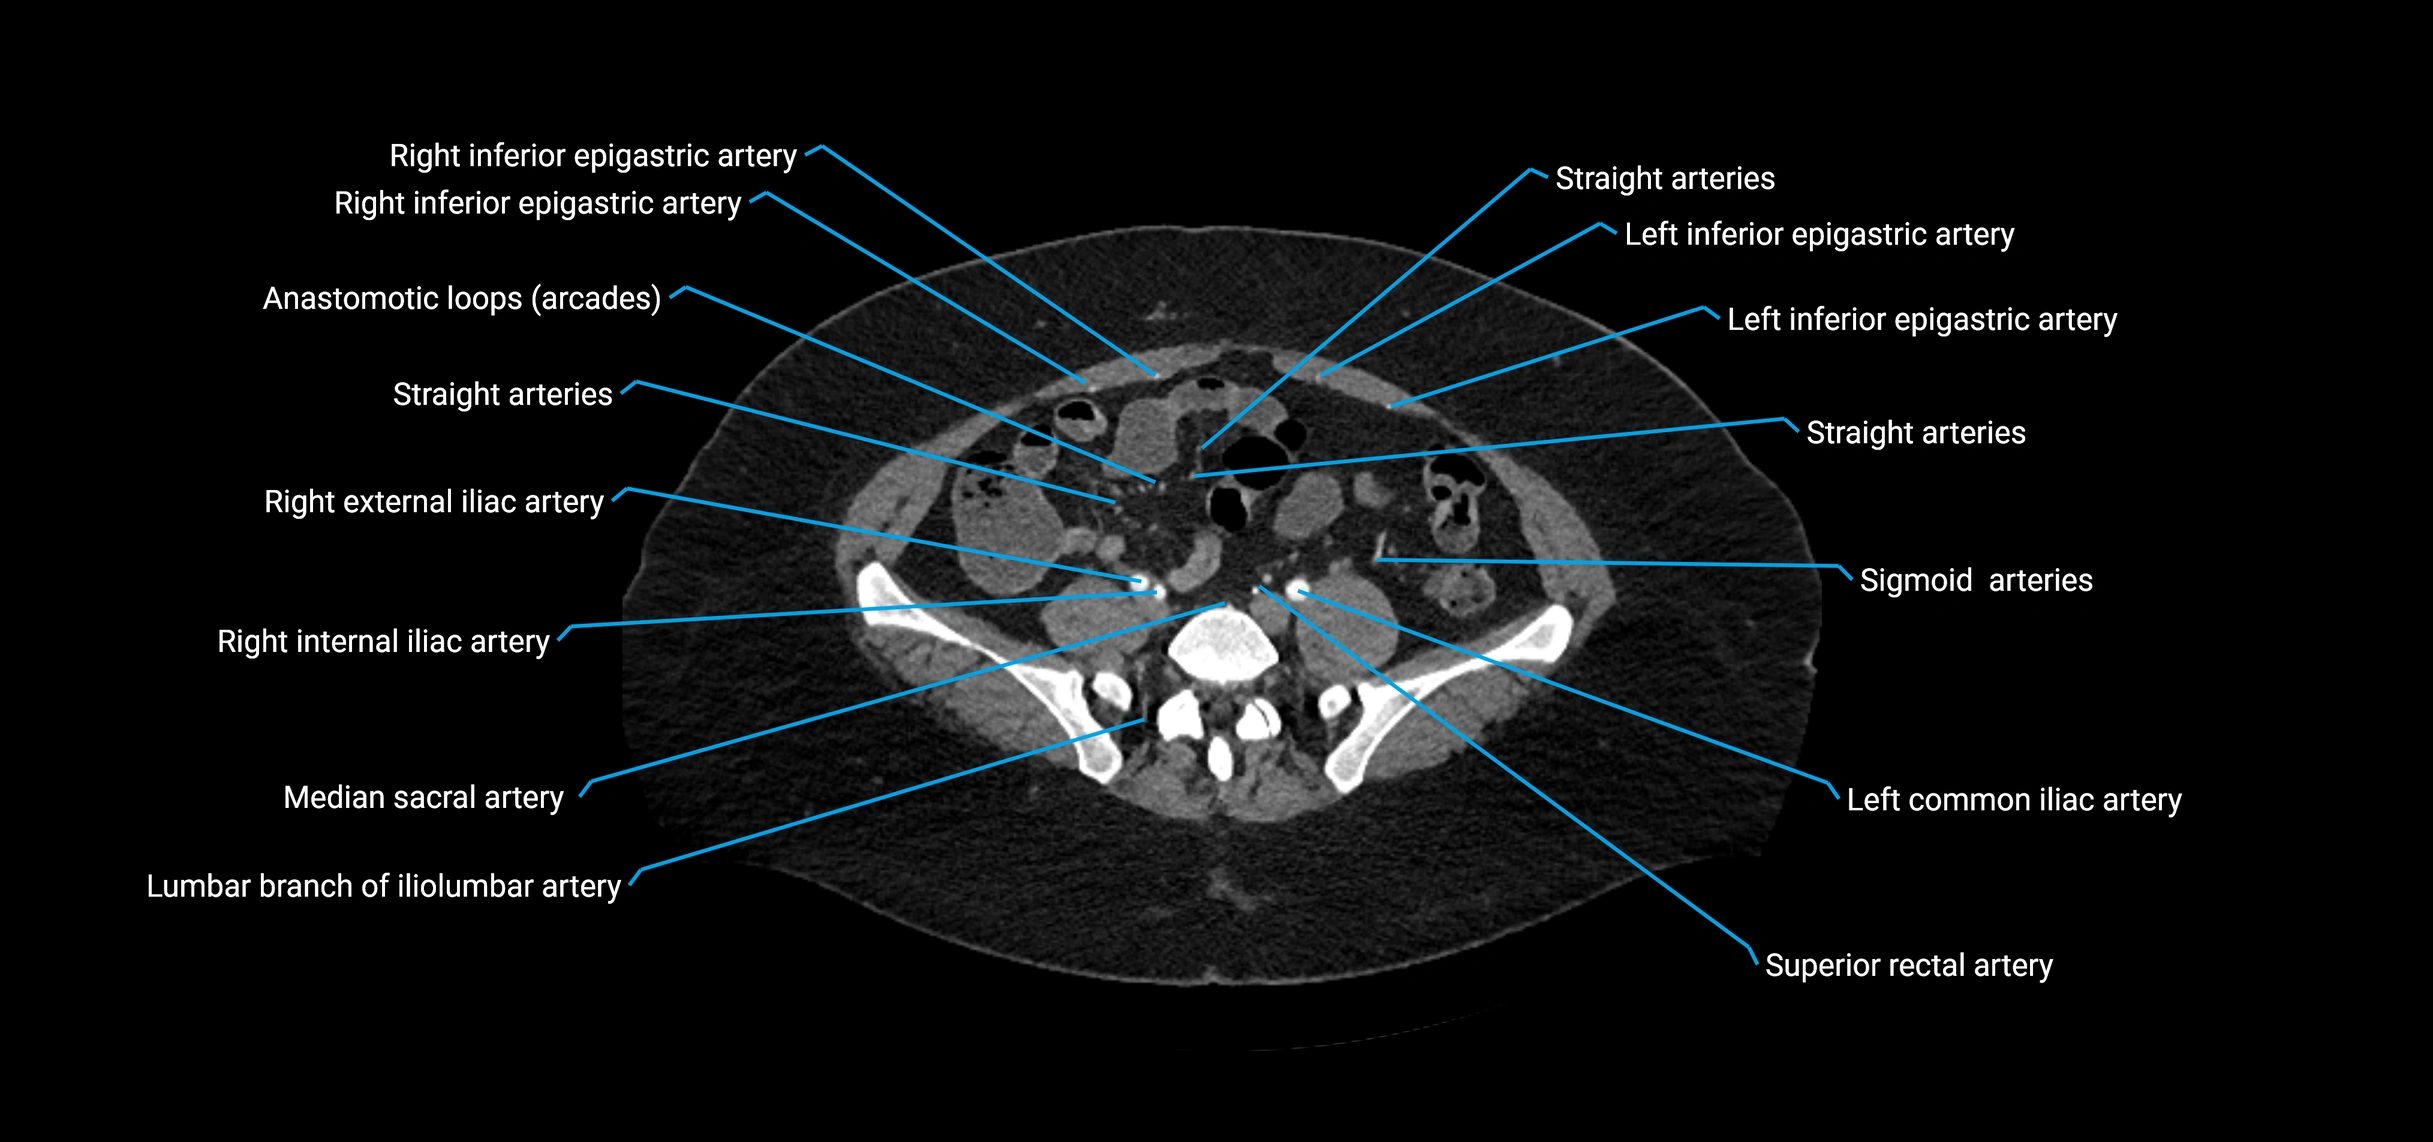

CT images

image

Contrast-enhanced CT (CTA):

• Gold standard for abdominal aortic imaging

• Provides excellent detail of lumen, wall, aneurysm, thrombus, and branch vessels

• Multiplanar and 3D reconstructions help in aneurysm measurement, stent graft planning, and dissection evaluation